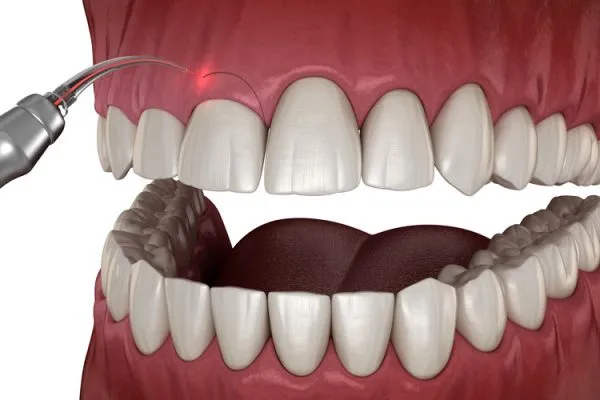

Solution : Gingivectomy, Lip Reposition

Solution : Gum Depigmentation